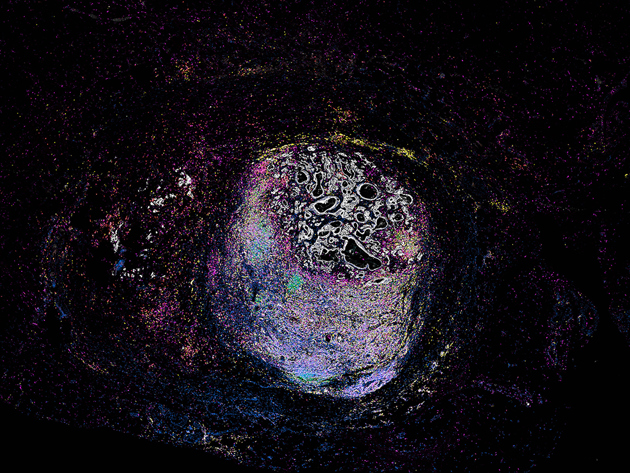

Huidweefsel was bepaald niet waar ze naar zocht door haar microscoop. Promovenda Emilia Pulver bestudeert de kanalen van mannelijke borstklieren en de vroege ontwikkeling van kanker daarin. Maar toen ze dit stukje huid zag, was ze gefascineerd. "Het deed me denken aan een duistere, mystieke kracht die de kijker naar dit griezelige, betoverde bos lokt", zegt Emilia. Ze komt uit Boston, VS, en voegde zich bij de onderzoeksgroep van Jos Jonkers vanwege zijn uitstekende reputatie op het gebied van diermodellen voor kankeronderzoek.

"Toen ik voor mijn onderzoek een keer een stukje weefsel bekeek, zag ik een groot stuk huid dat nog bovenop de borstklier lag. Het zag er best cool uit, dit 3D-landschap met al die diepte. Eerlijk gezegd zijn al mijn coolste beelden van andere structuren dan de kanalen die ik bestudeer, hoewel die buisjes ook mooi zijn."

No Man’s Gland